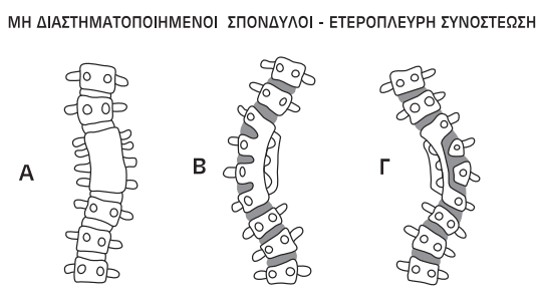

Οι ανωμαλίες διαστηματοποίησης μπορεί να είναι είτε ετερόπλευρες, όπως η μη διαχωρισμένη οστική γέφυρα (ετερόπλευρη συνοστέωση), ή αμφοτερόπλευρες, όπως ο αποκλεισμένος σπόνδυλος. Η ετερόπλευρη μη διαχωρισμένη οστική γέφυρα είναι η συχνότερη διαταραχή στη συγγενή σκολίωση. Αυτό συνίσταται σε οστική συγχώνευση της ανάντης και της κατάντης αρθρικής απόφυσης, καθώς και του σπονδυλικού δίσκου ετερόπλευρα, με συνέχιση της επιμήκους ανάπτυξης του σπονδύλου στην αντίστοιχη πλευρά. Συνοδεύεται δε συχνά από την ύπαρξη ημισπονδύλου στην αντίθετη πλευρά

Εικόνα 12 (Α,Β,Γ)